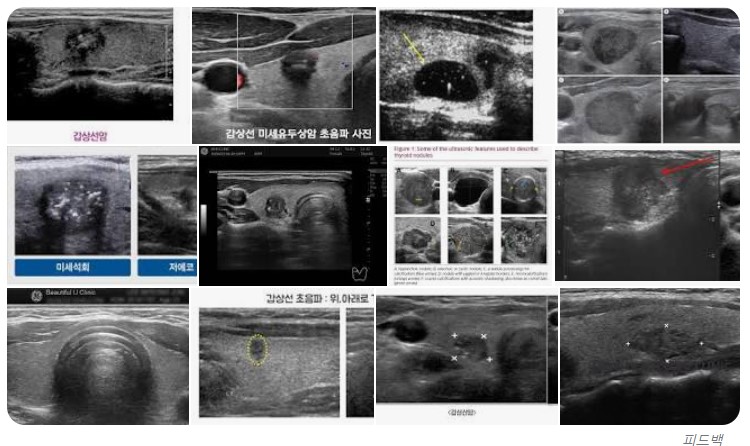

정기검진 초음파

초음파 할 때마다 긴장된다.

계속 사진을 찍는데 혹시 거기 재발한 건 아닌지 싶어 눈을 동그랗게 뜨고 초음파 화면을 보지만 나는 알 수 없다.

답답해서라도 초음파 사진 보는 연습을 하고 갈까? 싶을 때도 있다.

오늘도 집에 와서 구글 사진들을 찾아봤다.

갑상선 초음파 사진이라고 치고 봤는데 잘 모르겠더라는...

암처럼 보이는 게 암이 아니고 물혹 뭐 그런 거고... 암은 내 눈에는 오히려 아무 이상 없는 거처럼 보였다.

당연히 결국 포기!